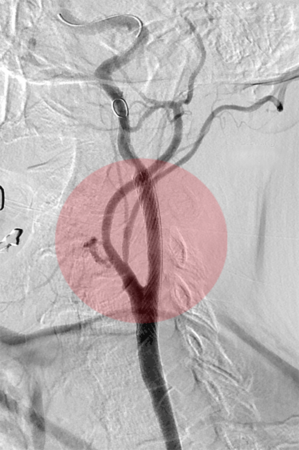

Behandlung der eingeengten Halsschlagader:

Patienten mit hochgradigen arteriosklerotischen Einengungen der Halsschlagader mit oder ohne Symptome eines Schlaganfalles, können neben der operativen Behandlung auch interventionell behandelt werden. Dazu wird ein Stent in die eingeengte Arterie eingesetzt. Ein spezielles Filtersystem verhindert dabei das Verschleppen von Wandablagerungen in die Hirnarterien und damit die Gefahr einer während der Behandlung auftretenden Durchblutungsstörung des Gehirnes.